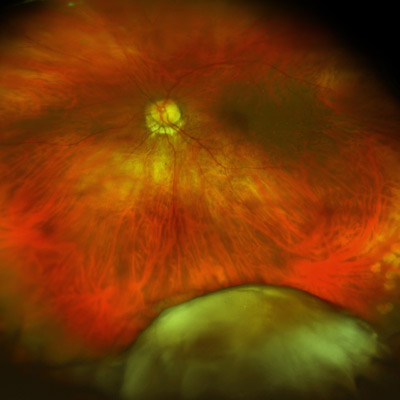

Handling a dropped nucleus

Dropped nuclei are one of the more unpleasant complications that can happen during cataract surgery. While uncommon, the consequences of a dropped nucleus are significant. Three experts shared their experiences and management strategy.